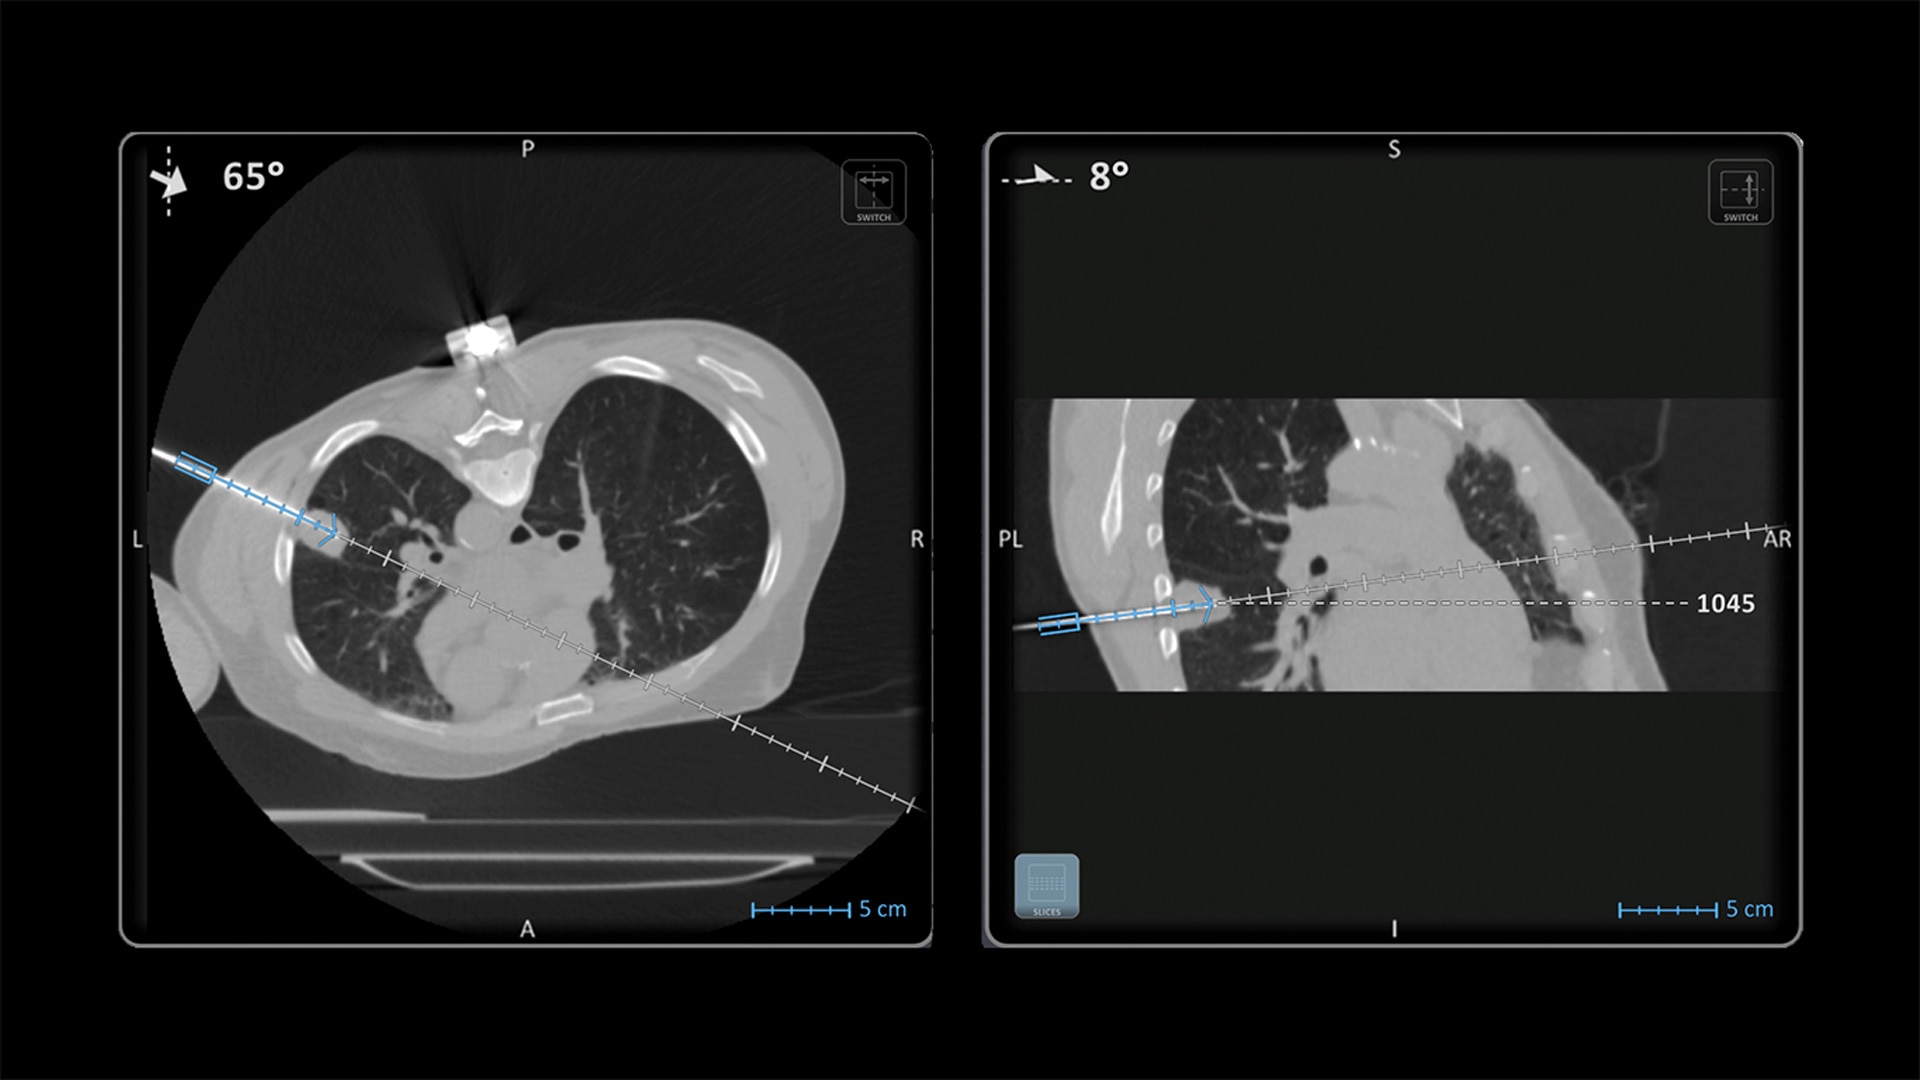

Accuracy

Improve accuracy to reach target and avoid critical structures and organs¹